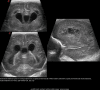

White matter injury (WMI) is the most frequent form of preterm brain injury. Cranial ultrasound (CUS) remains the preferred modality for initial and sequential neuroimaging in preterm infants, and is reliable for the diagnosis of cystic periventricular leukomalacia. Although magnetic resonance imaging is superior to CUS in detecting the diffuse and more subtle forms of WMI that prevail in very premature infants surviving nowadays, recent improvement in the quality of neonatal CUS imaging has broadened the spectrum of preterm white matter abnormalities that can be detected with this technique. We propose a structured CUS assessment of WMI of prematurity that seeks to account for both cystic and non-cystic changes, as well as signs of white matter loss and impaired brain growth and maturation, at or near term equivalent age. This novel assessment system aims to improve disease description in both routine clinical practice and clinical research. Whether this systematic assessment will improve prediction of outcome in preterm infants with WMI still needs to be evaluated in prospective studies.